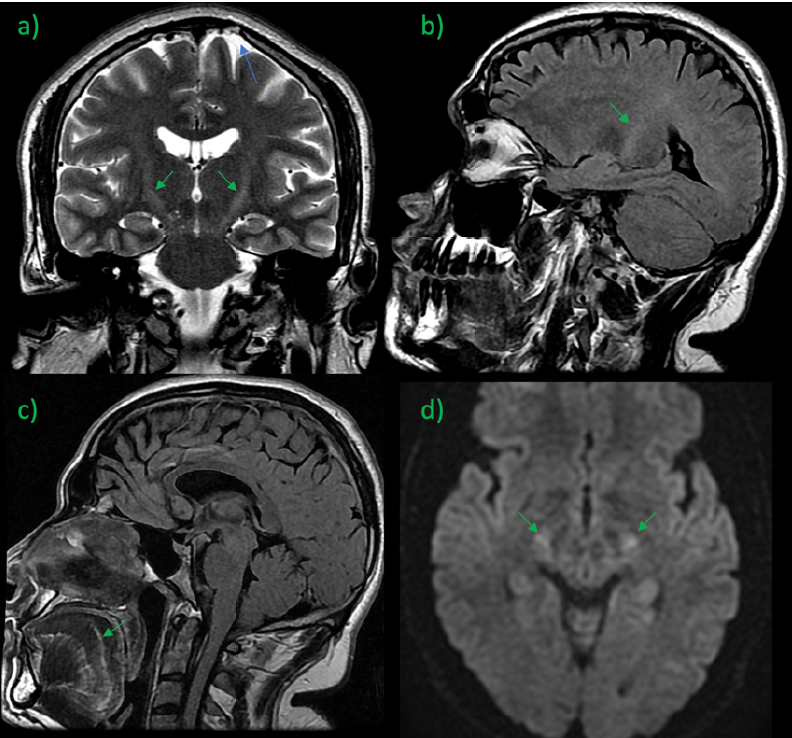

SARS-CoV-2 Unmasked Amyotrophic Lateral Sclerosis in a Genetically Predisposed Young Subject

Hector R Martínez, Carlos A Arreola-Aldape and Jose A Figueroa-Sanchez. 15(2): 12-17.